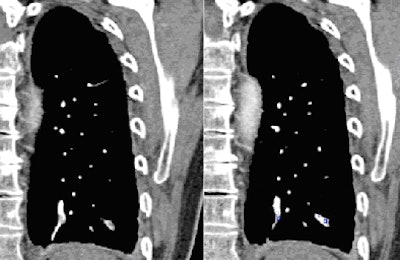

![]() |

| CAD identifies a false positive on the pulmonary vein. |